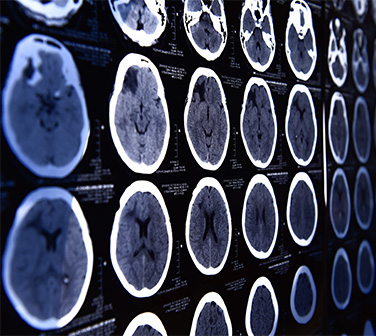

El desarrollo de las técnicas de neuroimagen actuales han permitido mejorar el conocimiento sobre la neurobiología del daño en el cerebro inmaduro, profundizar en los factores de riesgo y etiológicos y mejorar el diagnóstico.